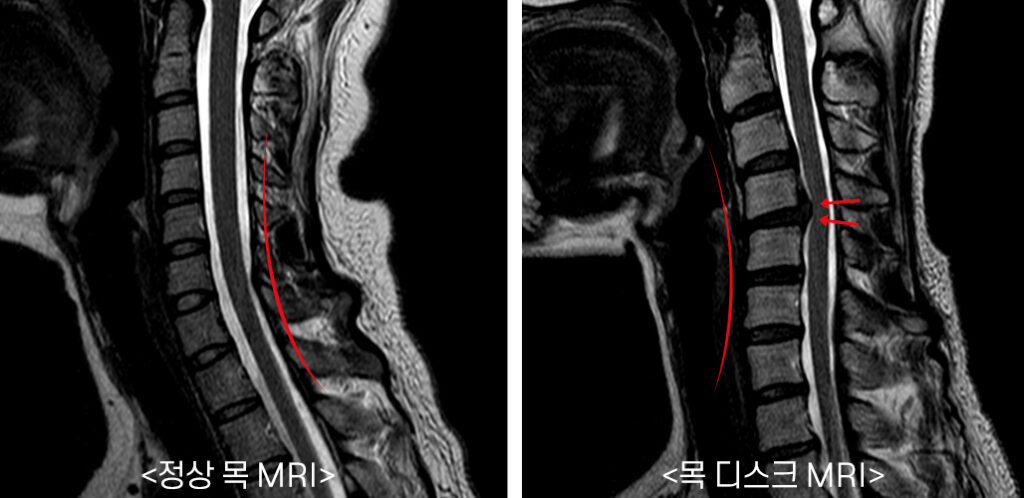

목디스크는 현대인들이 자주 겪는 문제 중 하나로, 그 증상은 다양한 형태로 나타납니다. 목디스크의 주요 증상으로는 통증, 마비, 약화, 두통 등이 있으며, 이러한 증상은 일상생활에 큰 영향을 미칠 수 있습니다.

목디스크의 가장 일반적인 증상은 목 부위의 통증입니다. 통증은 지속적이거나 간헐적으로 나타날 수 있으며, 목과 어깨를 움직일 때 더욱 심해질 수 있습니다. 특히 장시간 컴퓨터 작업이나 스마트폰을 사용하면 이러한 통증이 심해질 수 있습니다.

다음으로 나타날 수 있는 증상은 팔이나 손으로 방사되는 통증입니다. 목디스크로 인해 신경이 눌리면 팔로 통증이 전달될 수 있습니다. 이럴 경우 팔과 손의 감각이 떨어지거나 통증이 발생할 수 있습니다.

셋째, 마비감이 느껴질 수 있습니다. 목디스크가 신경을 압박하게 되면 어깨나 팔, 손에 불편한 감각이 나타나거나 마비되는 경험을 할 수 있습니다. 이는 일상생활을 아주 힘들게 만들 수 있습니다.